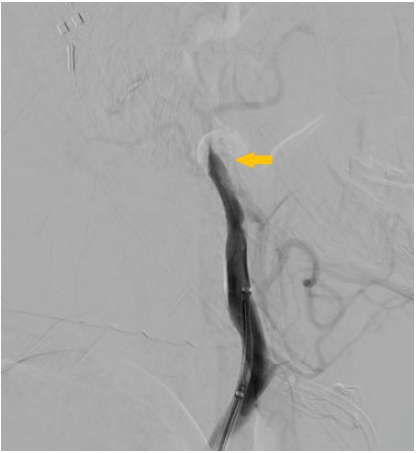

De nuestra serie de casos (n ¼ 228), solo se encontraron complicaciones en el 16,6%: hemorragias subaracnoideas secundarias a perforación (n ¼ 2) (►Fig. 1), hemorragia gangliobasal (n ¼ 1) (►Fig. 2), vasoespasmo (n ¼ 1), disección (n ¼ 1) (►Fig. 3), embolias (n ¼ 31) y pseudoaneurismas (n ¼ 2) (►Fig. 4) en el sitio de la punción. Cuando se detectó oclusión intracraneal (►Fig. 5), tras la trombectomía, dentro del grupo de las embolias, solo el 16,1% se presentaron hacia nuevo territorio vascular (arteria cerebral anterior) (►Fig. 6) o embolias distales. Debido al bajo número de complicaciones, se realizó un análisis mediante Fisher que da un resultado no significativo (►Tabla 3). Las hemorragias fueron subaracnoideas detectadas durante las trombectomías como la extravasación activa del contraste y corroborada mediante tomografía computada (TC) al finalizar el procedimiento. El vasoespasmo que se presentó fue moderado en arteria cerebral media izquierda que cedió tras la infusión intra-arterial de 0,2 mg nimodipino.

Proyección lateral de la arteriografía durante la trombectomía donde se evidencia extravasación activa del medio de contraste (flecha amarilla), en una rama de M2 en relación a la ruptura de vaso posterior a la trombectomía con dispositivo ERIC 3 (3 mm x 15 mm) con disección arterial proximal (flecha azul), con ausencia en flujo cortical parietal ipsilateral (área con círculo negro).

Arteriografía durante el acceso vascular del segmento cervical de la arteria carótida interna (ACI), extracraneal donde se evidencia disección oclusiva de la carótida interna cervical proximal.